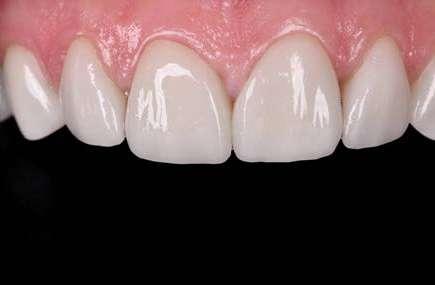

En la arcada superior por el contrario se decidió poner unas carillas de disilicato para poder cubrir las expectativas de la paciente y ajustar el color al que ella deseaba, bajando casi en 5 tonos el color final. Se planificaron preparaciones digitales conservadoras.

La preparación previa junto a la preparación guiada, resultaron en un equilibrio ideal para los espesores mínimos que requería el caso. Se realizó una prueba en seco para valorar el ajuste final de las restauraciones.

Consiguiendo así una perfecta adaptación de los márgenes de las restauraciones y la sensación de naturalidad e integración que se observa en la imagen final.

Como se puede observar en la imagen comparativa, la planificación se reproduce de una forma fiel a lo que se había planificado y aceptado por la paciente. Por tanto, no es una técnica susceptible al operador, que se realiza controlando mucho mejor los tiempos y los resultados obtenidos.